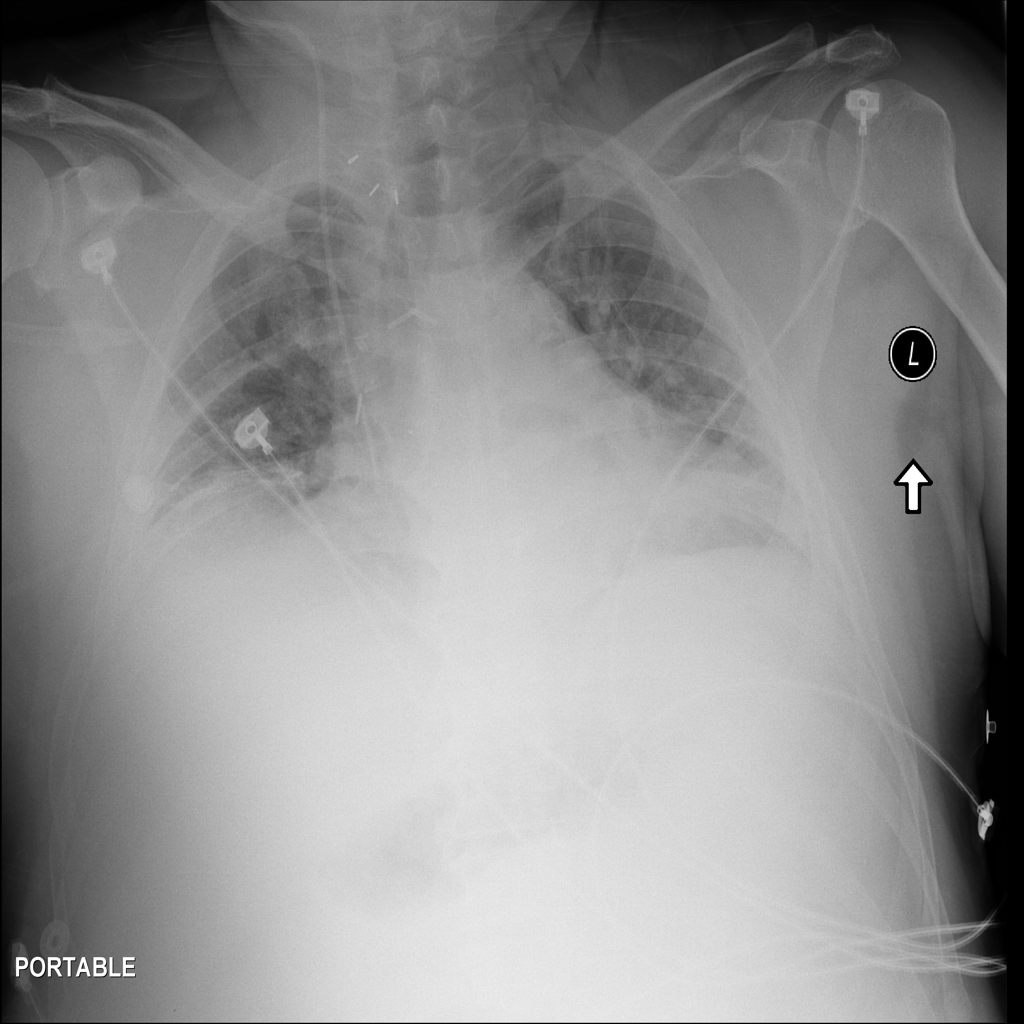

PAT-DB80 · IMG-001Atelectasis

PAT-DB80 · IMG-001

PA